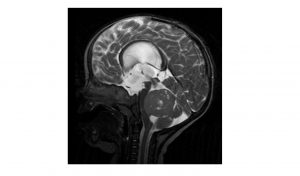

Mehr erfahren zu: "Hoffnung auf schonendere Therapie bei Hirntumoren" Hoffnung auf schonendere Therapie bei Hirntumoren Ein internationales Forscherteam hat eine Form des Medulloblastoms identifiziert, die besonders gute Heilungschancen aufweist. Rund 20 Prozent der Betroffenen könnten nach Schätzungen der Wissenschaftler unter dieser Variante leiden.

Mehr erfahren zu: "Manchmal nutzt vor der Therapieentscheidung ein Blick auf die Gene" Manchmal nutzt vor der Therapieentscheidung ein Blick auf die Gene Forscher des Hopp-Kindertumorzentrums Heidelberg (KiTZ) zeigen gemeinsam mit Kollegen aus den USA, welche molekularbiologische Vielfalt sich hinter scheinbar gleichartigen embryonalen Hirntumoren verbergen kann. Damit belegen sie, wie wichtig es sowohl […]